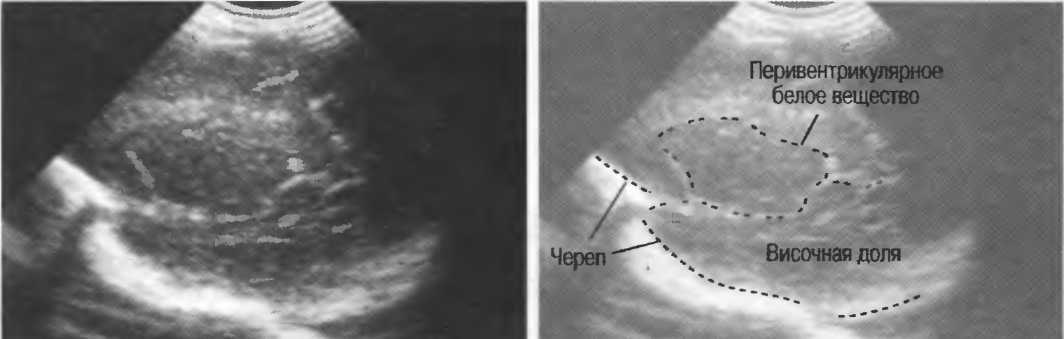

3. Ультразвуковые исследования в педиатрии. Для детей необходим датчик с частотой 5 МГц с глубиной фокусировки на 5-7 см. При исследовании мозга новорожденного используется секторный датчик с частотой 7,5 МГц с глубиной фокусировки на 4-5 см (этот датчик также используется для исследования яичек и структур шеи у взрослых).